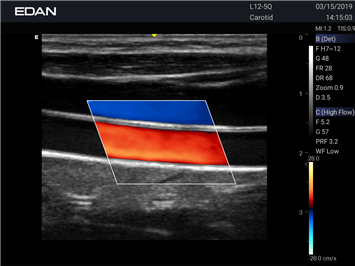

- Machine Type 4D Colour Doppler Ultrasound Machine

- Adaptive Doppler imaging Frequency Compounding Imaging ,- Adaptive Spatial Compounding Imaging ,- Harmonic Imaging ,- Adaptive Speckle Reduction Imaging (eSRI)

- Spectrum Enhancement ,- B mode Auto Optimization ,- Color mode Auto Optimization

- PW mode Auto Optimization